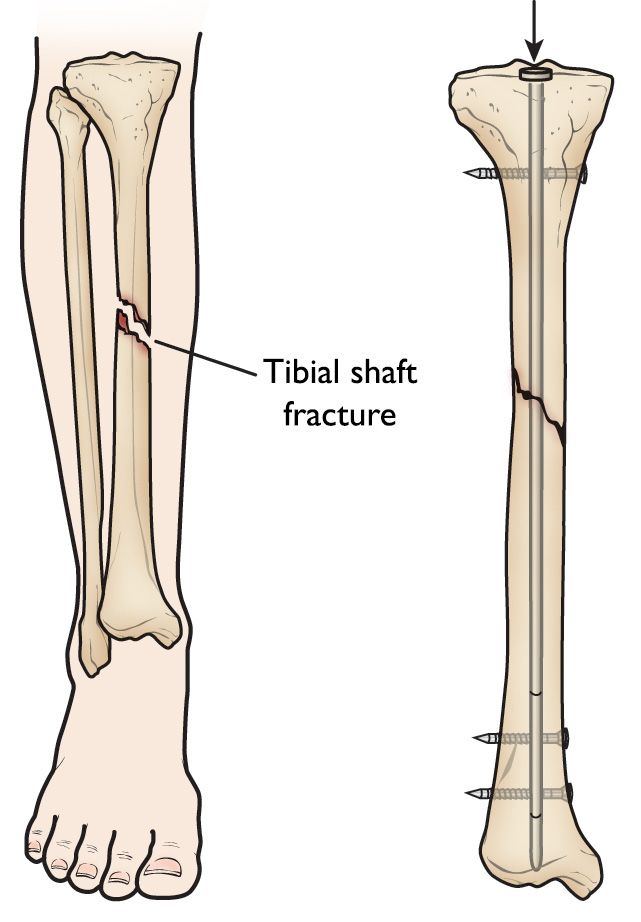

Lower leg anatomy and tibial shaft fracture

The tibia is the larger bone in your lower leg. Tibial shaft fractures occur along the length of the bone.

Intramedullary nailing of a tibial shaft fracture

Intramedullary nailing provides strong, stable, full-length fixation.